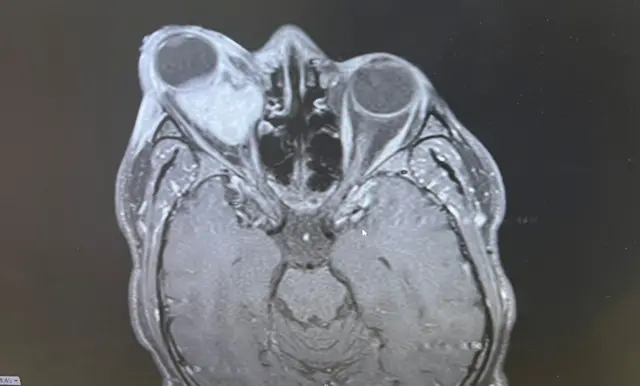

Зрештою зробили МРТ, і лікарі повідомили Оладапо, що в нього пухлина.

Біопсія, проведена під час операції, показала, що це ембріональна рабдоміосаркома – рідкісний тип раку м’яких тканин.